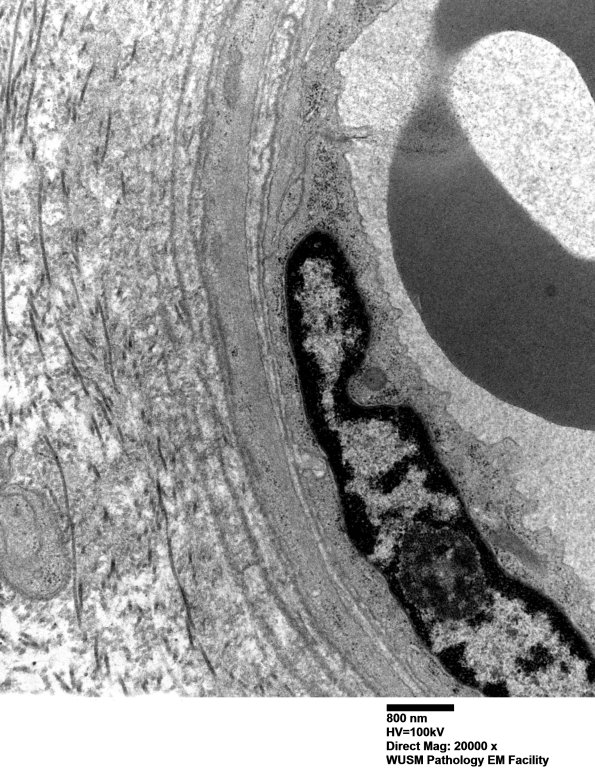

Washington University Experience | VASCULAR | Hypoxia-Ischemia, fetal-neonatal | White Matter | 17B5 (Case 17) HIEM EM019 - Copy

17B5 (Case 17) HIEM EM019 - Copy